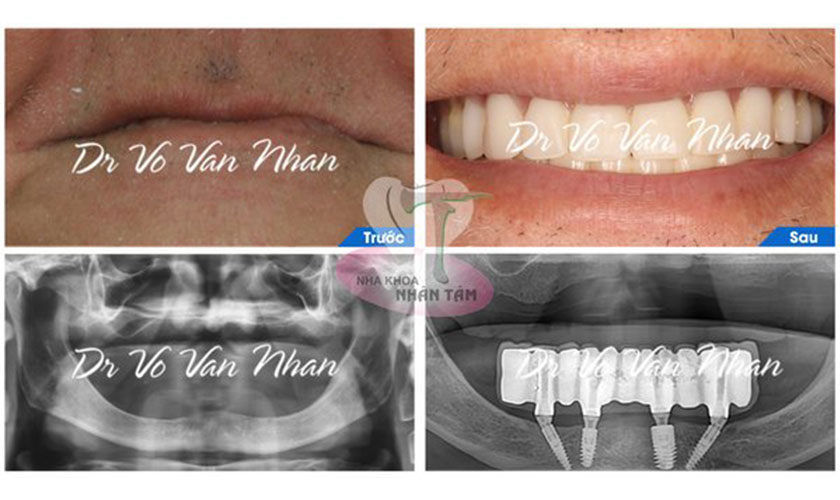

Nha khoa Nhân Tâm là địa chỉ cấy ghép Implant uy tín hàng đầu tại TP.HCM

- Đội ngũ bác sĩ, trợ thủ nha khoa có trình độ chuyên môn cao, giàu kinh nghiệm, đứng đầu là Ts.Bs Võ Văn Nhân – một trong những chuyên gia hàng đầu về cấy ghép Implant tại Việt Nam với hơn 25 năm kinh nghiệm.